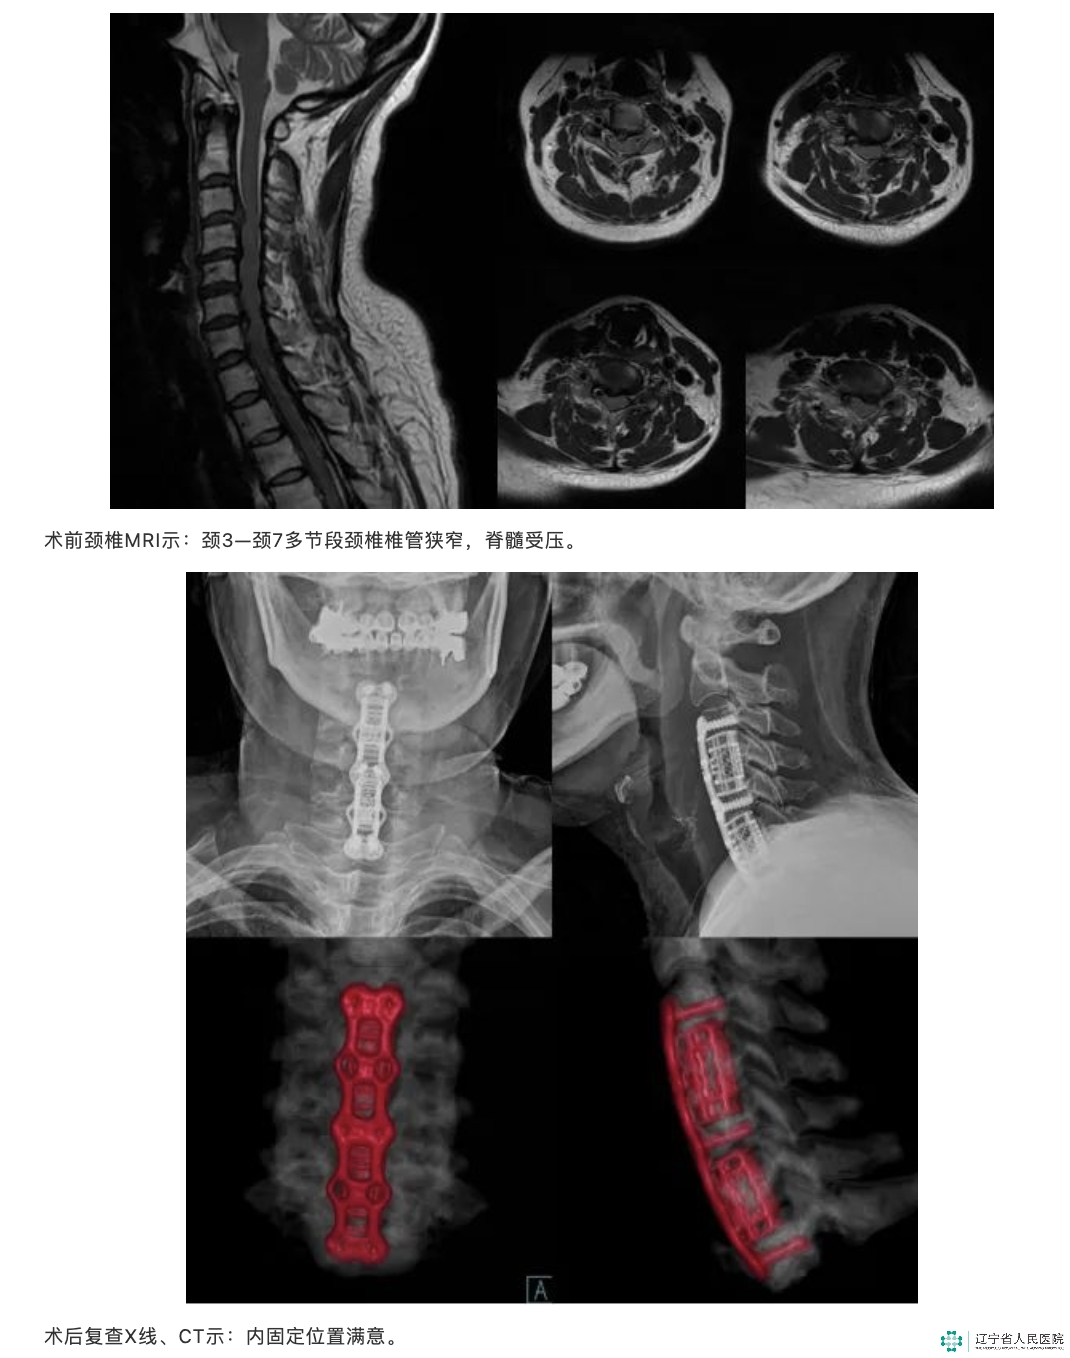

近日,我院骨五科刘军、任伟剑团队顺利完成一例多节段颈椎前路手术。

刘军、任伟剑团队经过详尽的术前讨论,确定手术方式为颈椎前路手术。术后症状缓解明显,陈大姐术后顺利出院。